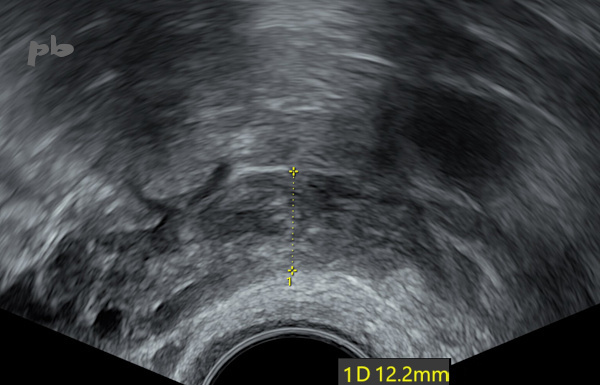

43 – GEU et salpingostomie

GEU gauche (sac gestationnel intra-tubaire) traitée par salpingostomie, à J4 post-chirurgie.

Baisse des B HCG, mais persistance des douleurs.

Echographie endovaginale.

La trompe (entre les croix) reste épaissie, hétérogène, mais de calibre régulier : simples caillots.

Normalisation clinique et échographique rapide.

43 – Ectopic pregnancy and salpingostomy

Left ectopic pregnancy (intra-tubal gestational sac) treated by salpingostomy on day 4 post-surgery.

Decrease in β-HCG levels, but persistence of pain.

Transvaginal ultrasound.

The tube (between the crosses) remains thickened, heterogeneous, but with a regular caliber: simple clots. Rapid clinical and ultrasonographic normalization.